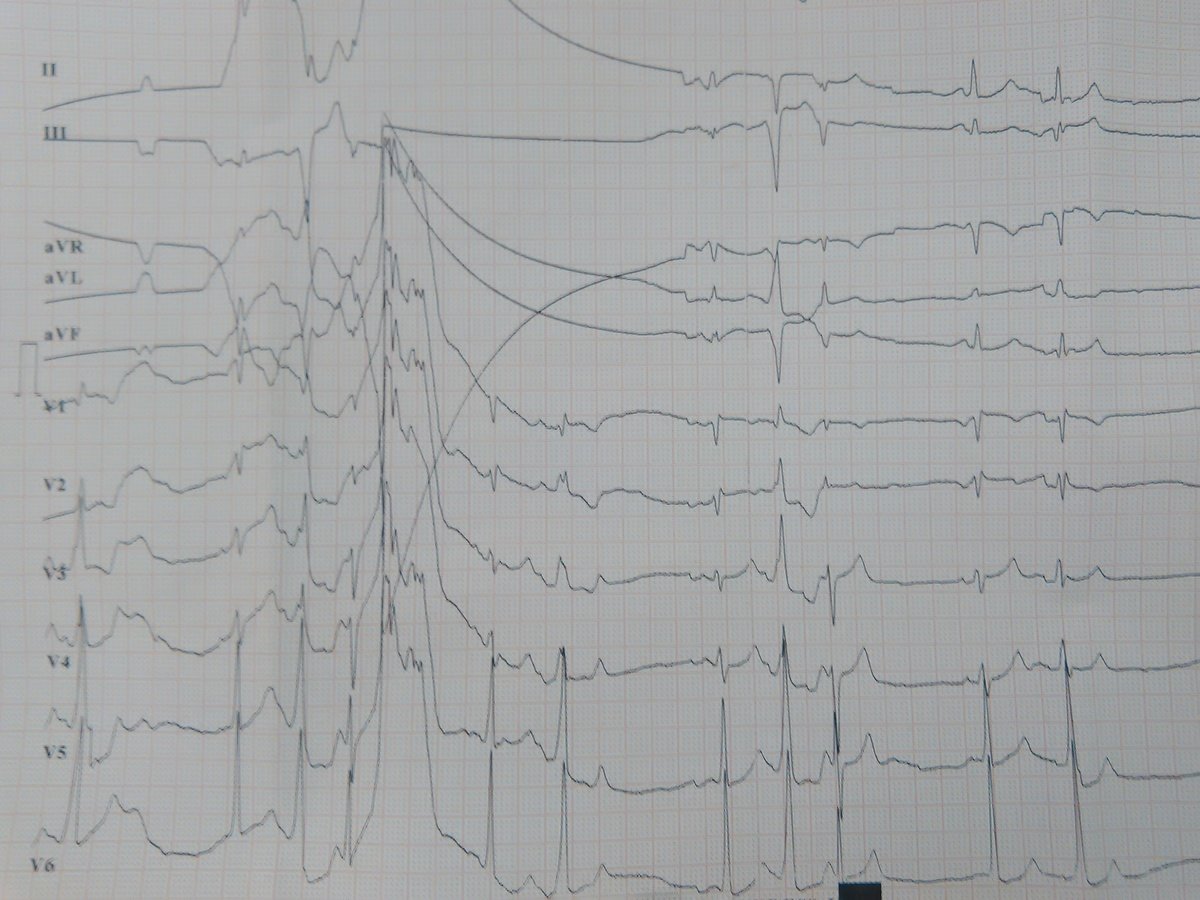

WPW syndrom

známky preexcitace na povrchovém EKG + anamneza palpitací/ záchyt tachyarytmie